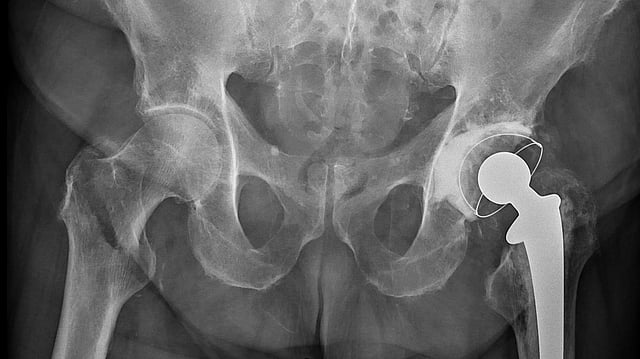

Hip fractures are especially dangerous for older patients, usually resulting from falls. Representational Image: Wikimedia Commons

Her tumble caused extensive damage to her hip bone, and she was taken by her family to the hospital in an emergency. "Surgery at this age carries significant risks and complications, but she has responded well to the procedure," said Dr. Anurag Dhaker, who led the surgical team. "We implanted a prosthetic component to repair the fractured area, which involved replacing the hip joint ball. She will regain her ability to walk," he added.

Given the potential complications of prolonged immobility, doctors proceeded with the surgery rather than leaving the fracture untreated. Without medical intervention, she could have been confined to bed, increasing the risk of respiratory problems, bedsores, urinary tract infections, and pneumonia. Dr. Dhaker said that hip fractures are especially dangerous for older patients, usually resulting from falls and exacerbated by osteoporosis, a weakening of the bones. Injuries like this can have serious implications for health, mobility, and overall quality of life. Her age makes this case stand out. Studies have shown that despite the successful treatment of hip fractures, the fractures have a long-term impact on mobility and health, generally affecting mortality rates in older individuals.